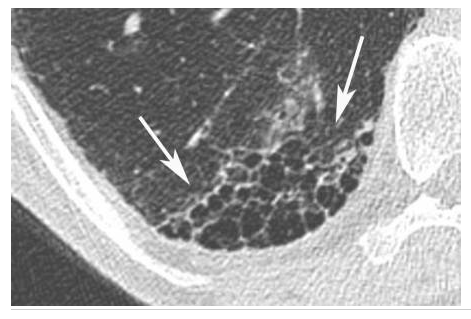

Pneumopathie d’hypersensibilité.

Agrandissement sur le sommet droit d’une coupe frontale. Micronodules à limites floues (flèches) de distribution diffuse dans les deux poumons. Leur topographie centrolobulaire est attestée par l’absence de micronodules sous-pleuraux (têtes de flèches).